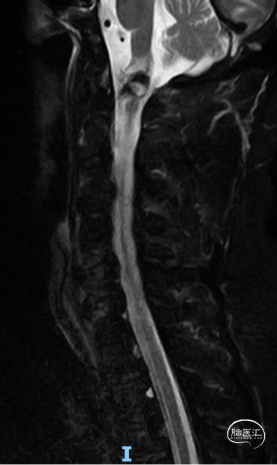

术前颈椎MR

CCJ AVF 栓塞后复发,术区及以下脊髓水肿,变性

术后一周MR,提示脊髓水肿较前减轻